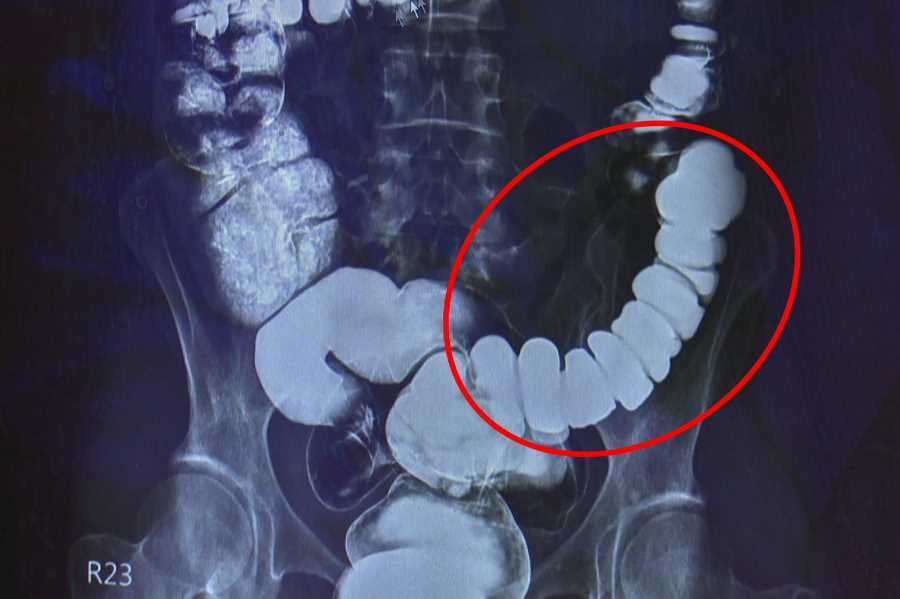

邱建銘從大腸攝影檢查發現,江小姐腸子繃得非常緊。這類典型情緒影響腸道的病例,臨床不算少,邱建銘仍驚訝說:「沒看過把自己腸子逼得這麼緊的。」邱建銘耐心問診,得知病人易焦慮的個性及澳洲生活與求診的坎坷,才確認需要手術解決。

他保留江小姐一小段升結腸,以腹腔鏡切除大部份大腸,再吻合升結腸與乙狀結腸,減少術後嚴重腹瀉或夜間滲便,也減緩嚴重便秘。家人看見切除的腸子緊縮成一團,才理解江小姐多年來的痛苦並非無病呻吟。江小姐術後在病房含淚擁抱邱主任,感恩他用心用愛解除病苦。